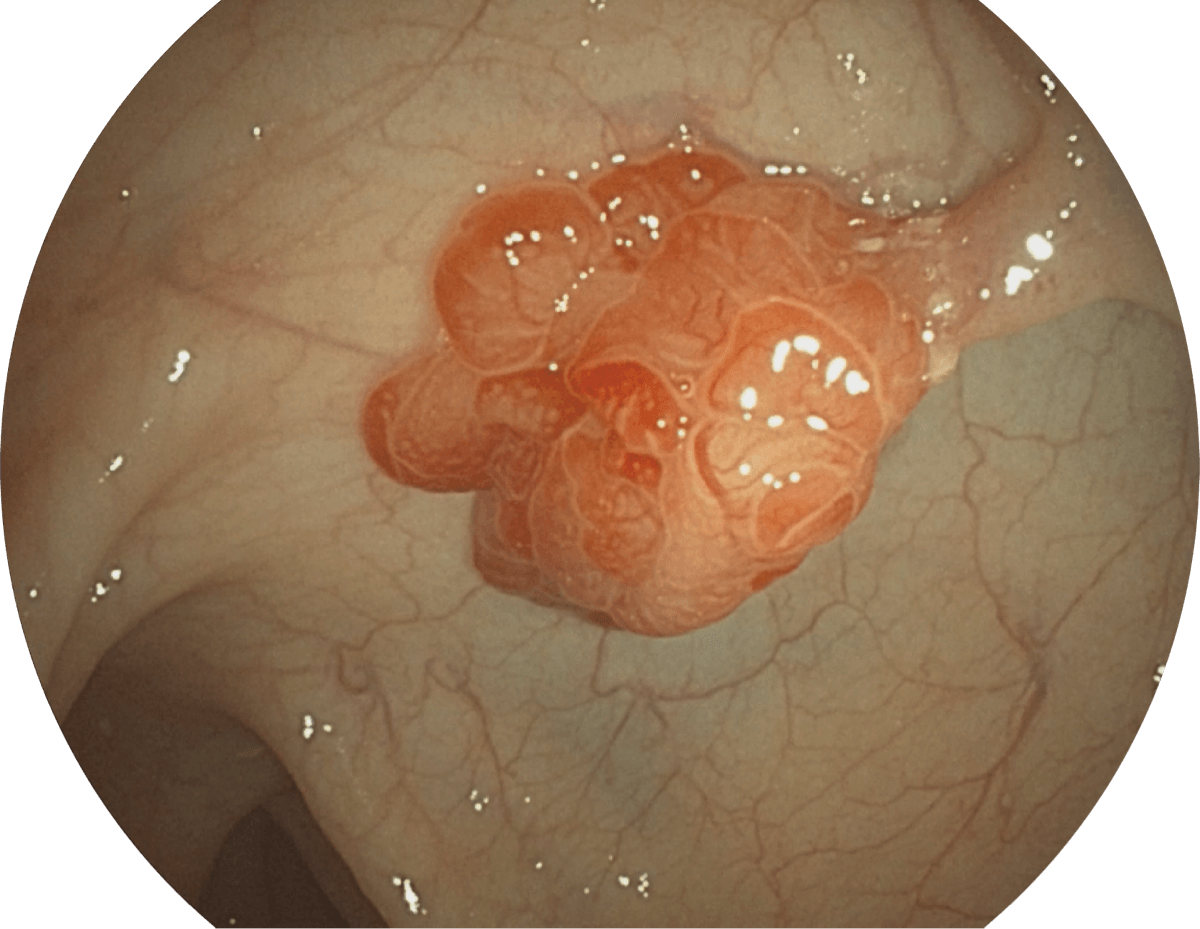

具有聚谱成像技术(SFI)及光电复合染色成像技术(VIST),可完美呈现粘膜细节及病变特征。

(Spectral Focused lmaging, SFI)

WL

SFI